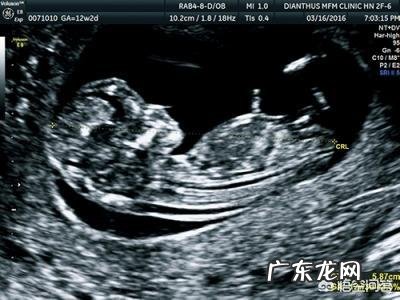

孕三个月,胎儿的长度还算腿和脚吗为什么【38周胎儿体重还会长吗一般多少斤】怀孕三个月,胎儿的长度还算腿和脚吗?当然不算咯,这时候根本不需要测量胎儿的腿和脚,只需测量头臀径就行 。先来看一下怀孕三个月胎儿的样子,也就是孕12周 。

此时B超测量的往往是胎儿的头臀径 。顶臀径:又称头臀长(CRL),指胎儿从颅顶顶部到臀部外缘的距离,一般怀孕7-12周左右测量 。

超声检查早孕胎儿时,常用顶臀径估测胎儿的孕龄,此为最为准确的估测方法 。故此采用以下公式计算妊娠龄 。公式: 妊娠龄(周)=CRL(cm)+6.5 。

产检小百科:怀孕12周宝妈不要忘了做NT检查哦,虽然不是必检产检项目,但是对于筛查胎儿染色体异常或胎儿结构异常还是很重要的 。

总结,怀孕12周时根本不需要测量肢体,只要测量头臀径就行 。祝好孕 。